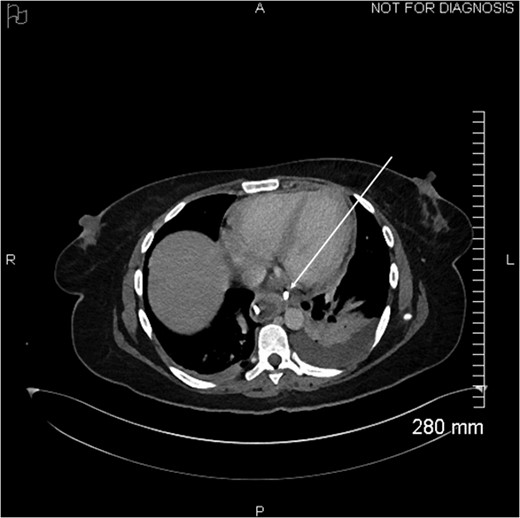

Coronal view of opacification on CT showing the externalization of the drain in the pericardium (arrow).